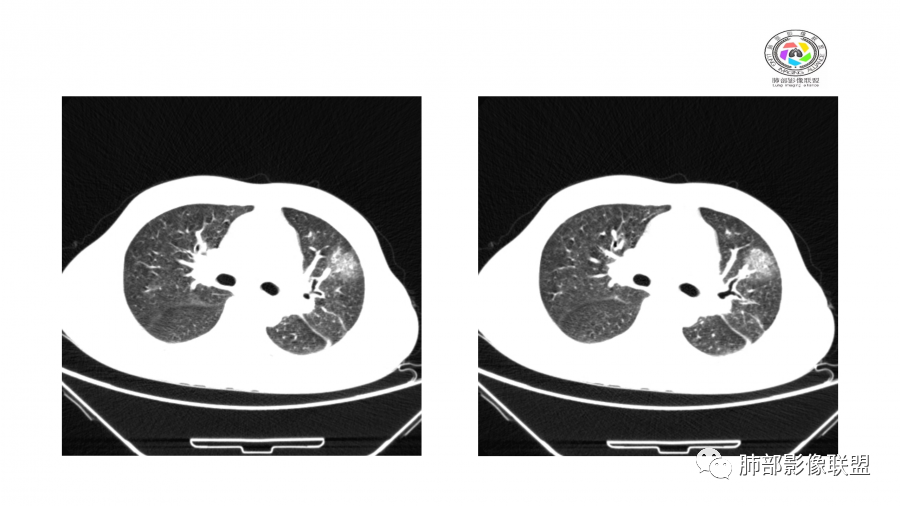

胸部CT:双肺多发实性斑片影,散在GGO。实性斑片周围可见晕征、边缘模糊不清,病灶于肺外围区域优势分布。肺门区血管影增粗,支气管套袖,目测肺动脉增粗。3月、4月复查肺内实性斑片病灶呈游走性,此起彼伏。

两肺多发团片状高密度影

南边:

边界模糊,距离胸膜有间隙,内部支气管通畅

10天后:病灶继续吸收好转

伴随少量胸水

应该与气道无关

符合间质、血管来源病变

此起彼伏